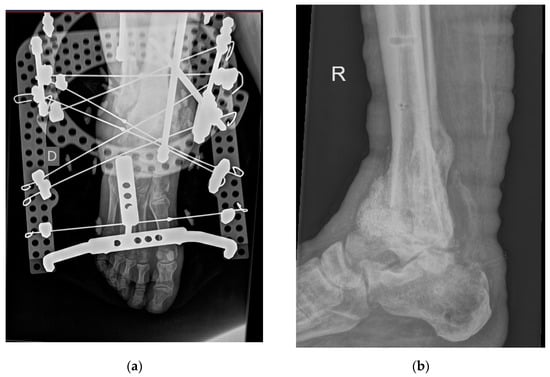

Out of the four cases presented in this group, three were reported to suffer from Charcot neuroarthropathy and all had confirmed septic osteoarthritis. Table 1 shows their detailed characteristics, including significant concomitant diseases documented. For two patients, the procedure was single-phase, with resection of the affected bone and joint and insertion of BAG in the form of granules and putty. One patient received multiphase surgical treatment and, in the ending phases, the application of BAG into the talocrural and subtalar joint and an external fixator. In all patients, an external fixator device was used; in two cases, an Ilizarov round fixator was used. Figure 3 demonstrates the use of an Ilizarov fixator and intraoperative placement of BAG granules and putty as well as the extent of osteointegration in the talocrural joint after eight months.

Figure 3.

(a) Patient after insertion of bioactive glass granules and putty (malleolus) with an Ilizarov external fixation device. Image captured with Siemens Polydoros SX80® (Siemens, Munich, Germany); (b) patient after removal of Ilizarov external fixation device (eight months after insertion of bioactive glass granules and putty). Image captured with Philips Digital Diagnost® (Philips, Amsterdam, The Netherlands) (exposure parameters: 68 kv and 4 mAs).

The same three patients received at least six weeks of concomitant antibiotic therapy. The mentioned three patients suffered no early or late complications.

The fourth patient suffered late complications. The patient suffered from Charcot neuroarthropathy. Initially, septic osteoarthritis of the ankle was treated in two phases. First, resection of the ankle joint was performed with placement of a gentamycin bead chain as well as placement of an external fixator. After three weeks, the gentamycin bead chain was replaced with BAG granules and putty. According to the antibiogram, they received intravenous antibiotic treatment for three weeks and additionally another six weeks perorally. They were discharged one month after surgery and checked up every month for three months. However, for the next three months, the patient skipped planned checkups. Seven months after surgery, they came back with a fistula at the lateral ankle side. They rejected hospitalization and were urgently admitted four months later with signs of systemic infection and Staphylococcus aureus sepsis. Lifesaving supramalleolar amputation was performed. Subsequently, the patient was treated in a surgical intensive care unit. After stabilization and resolution of systemic infection, a below-knee amputation was performed with primary closure of the stump, the postoperative wound being without signs of infection and healing as per primary intention.